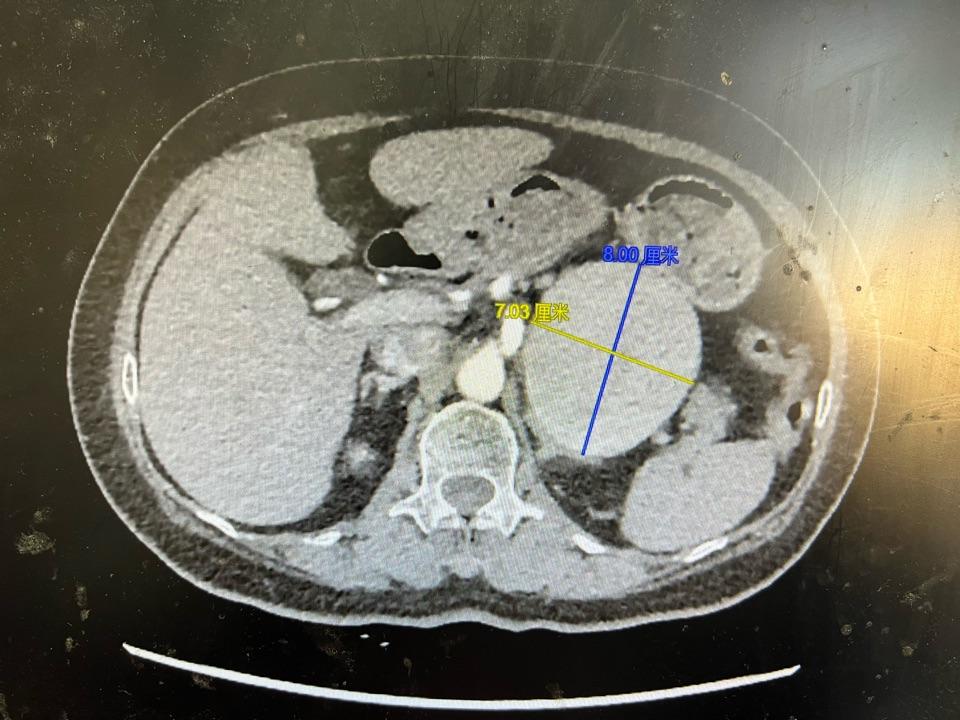

罕见的巨大脾动脉瘤的弹簧圈栓塞术

老年女性,做胆囊手术前发现脾动脉巨大动脉瘤,最大直径为8cm~7cm,转入我科急诊处理。

局麻微创行脾动脉瘤弹簧圈栓塞术,手术顺利,费时1小时,危机解除,患者卧床24小时后,顺利出院。